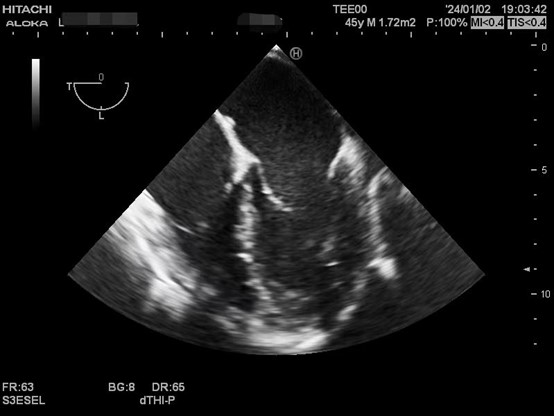

肝硬化患者术前合并症较多,术中血流动力学波动剧烈,围术期可能发生严重低血压、心内血栓形成、肺栓塞、左室流出道梗阻、心室收缩舒张功能不全等危急事件,给麻醉管理带来巨大挑战。TEE是将超声探头放在食管中段或胃底,从心脏后方持续观察心脏结构和功能,避免肺气对成像的影响,图像清晰且不影响手术的操作,是肝移植术中重要的监测手段之一。美国心脏超声协会及美国心血管麻醉医师学会均推荐肝移植术中常规使用TEE。目前美国各大移植中心术中麻醉科术中常规使用TEE进行持续监测。

以下是肝移植术中TEE监测的图像。